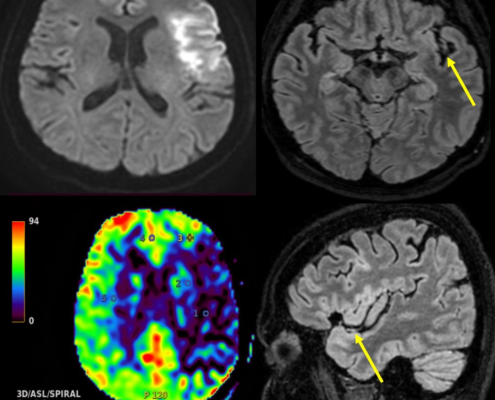

Carine Legio2023-02-03 08:00:482023-01-31 14:25:35Slow-flow in acute ischaemic stroke